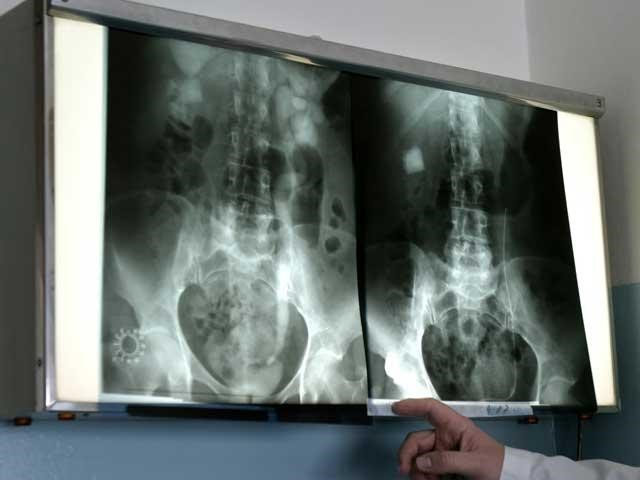

Как делают рентген? Обследование поясницы обычно проводят в двух проекциях – передней и боковой. Для этого пациента сначала укладывают на спину, а потом просят перевернуться на левый бок. В зависимости от предполагаемой патологии снимок делают либо общий, т. е. всего пояснично-крестцового отдела, либо прицельный, фиксирующий определенную часть данной части позвоночника.

Обследование поясницы обычно проводят в двух проекциях – передней и боковой

На снимке, полученном при рентгене, позвоночник представлен в виде столба, состоящего из единичных позвонков. Межпозвонковые диски, соединяющие их, заметны не так четко, т. к. хрящевая ткань более мягкая. Но даже пятна светлого оттенка позволяют увидеть различные патологии, которым подвержена данная структура.